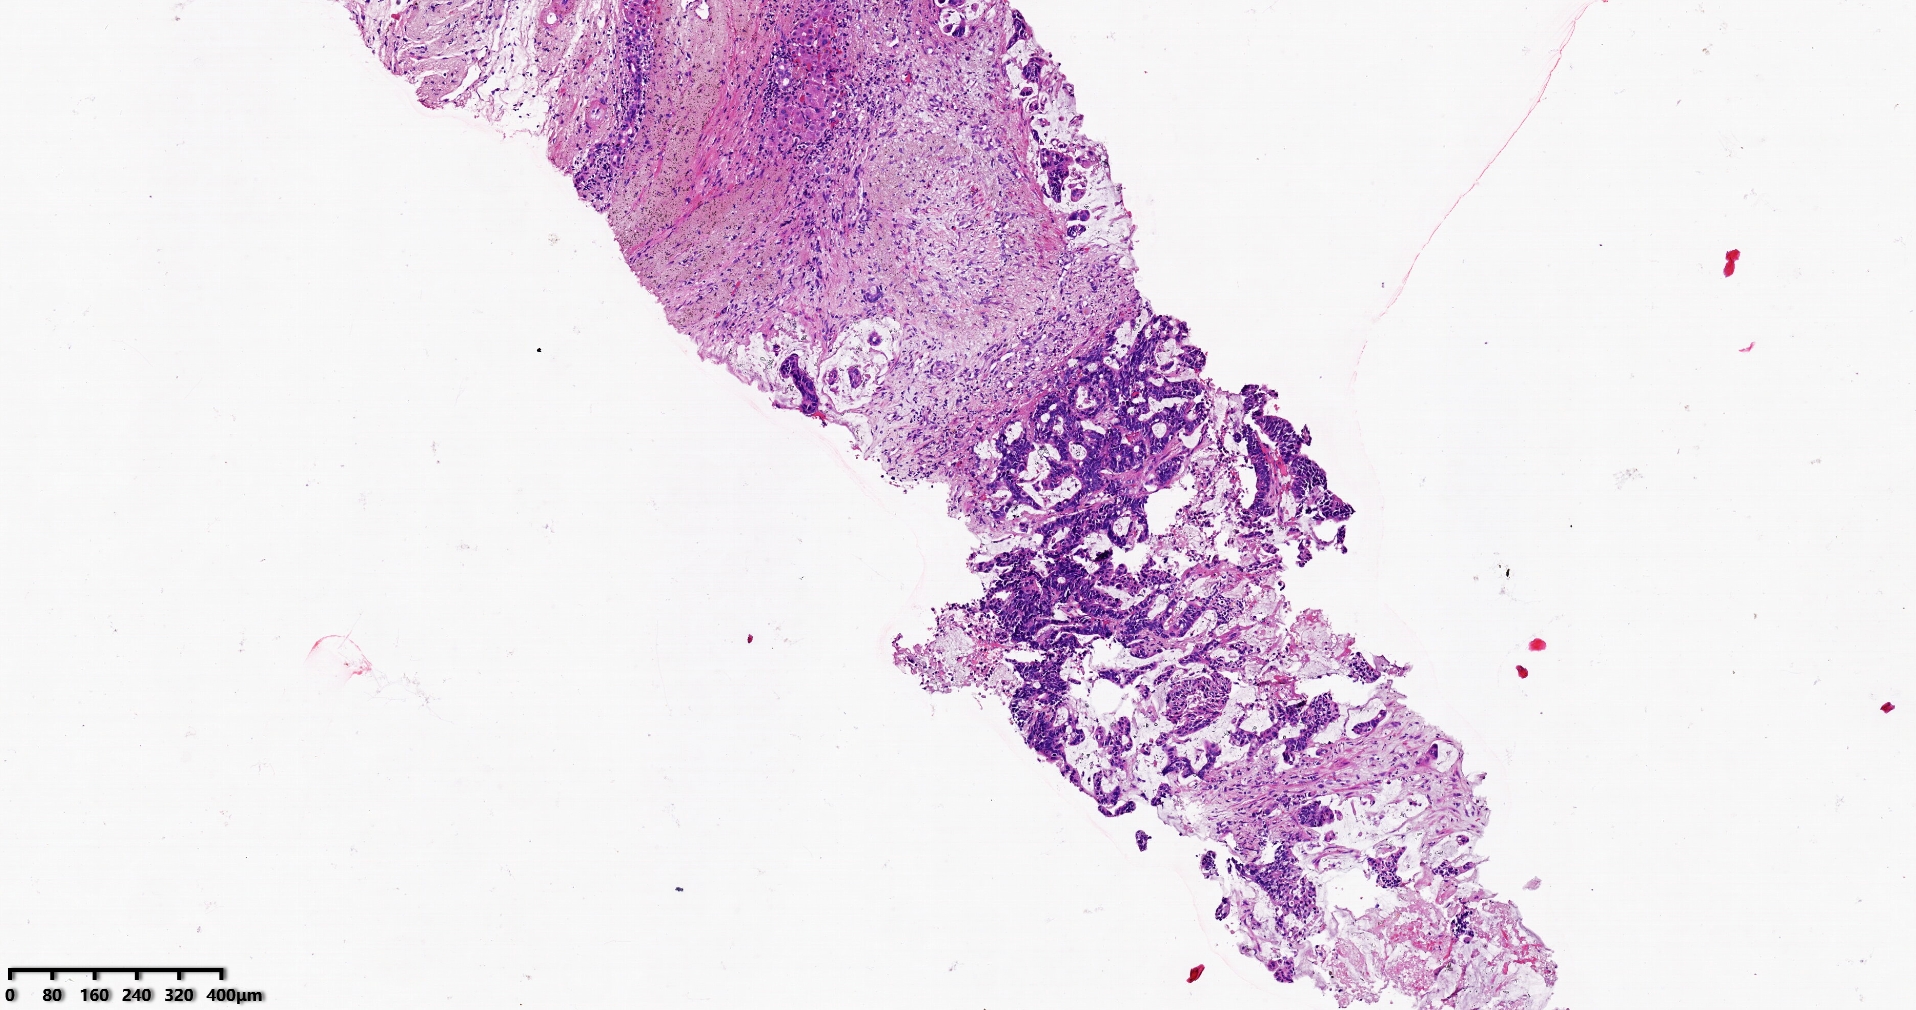

标本名称肝脏穿刺

大体所见灰白灰红色穿刺活检组织两条,长1.7-1.9cm,直径0.1-0.2cm。

考虑符合:肝内胆管癌

考虑转移性黏液腺癌,消化道来源可能,建议做免疫组化,排除胆管源性。